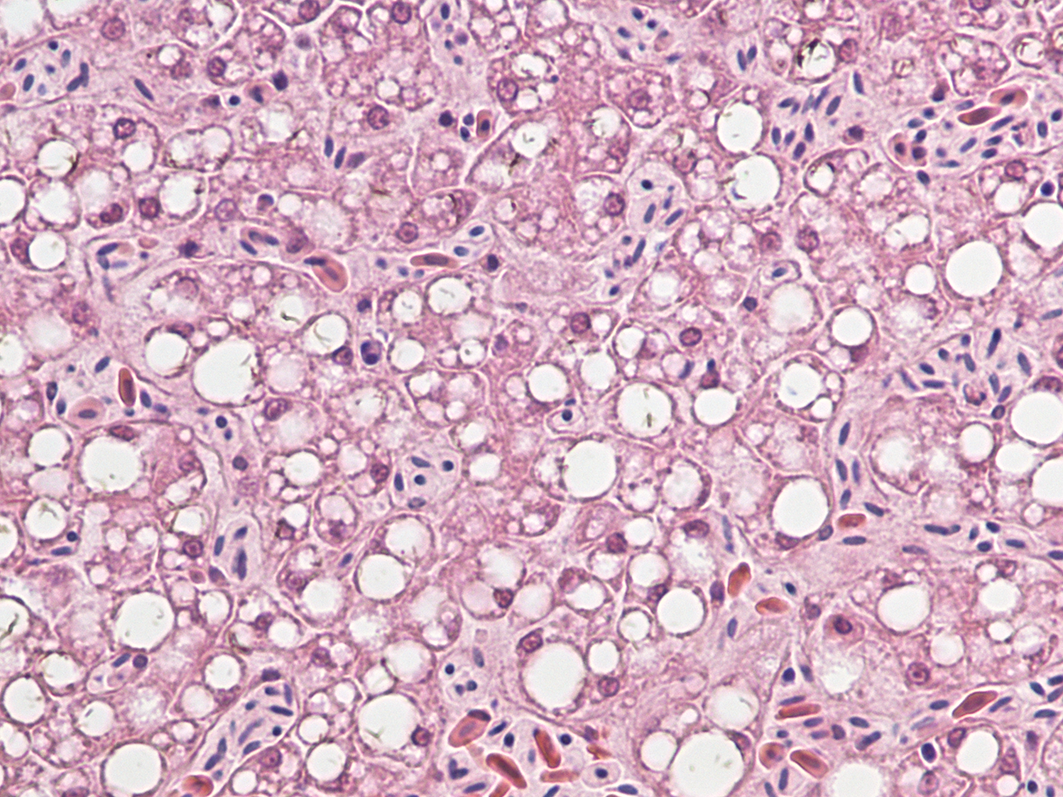

Officials at the USGS National Wildlife Health Center conducted necropsies to determine the cause of death and found liver damage in most of the birds. Damage to brain tissue was also common. Searches for environmental toxins underlying the disease came up empty.

“It is curious that the liver pathology of the eagles resembles the damage to human livers caused by hepaciviruses,” says White, branch chief for wildlife epidemiology and emerging diseases at the USGS National Wildlife Health Center. “But since the lesions are nonspecific there’s more that needs to be explored if we want to understand the virus itself or really get at what is the cause of WRES.”